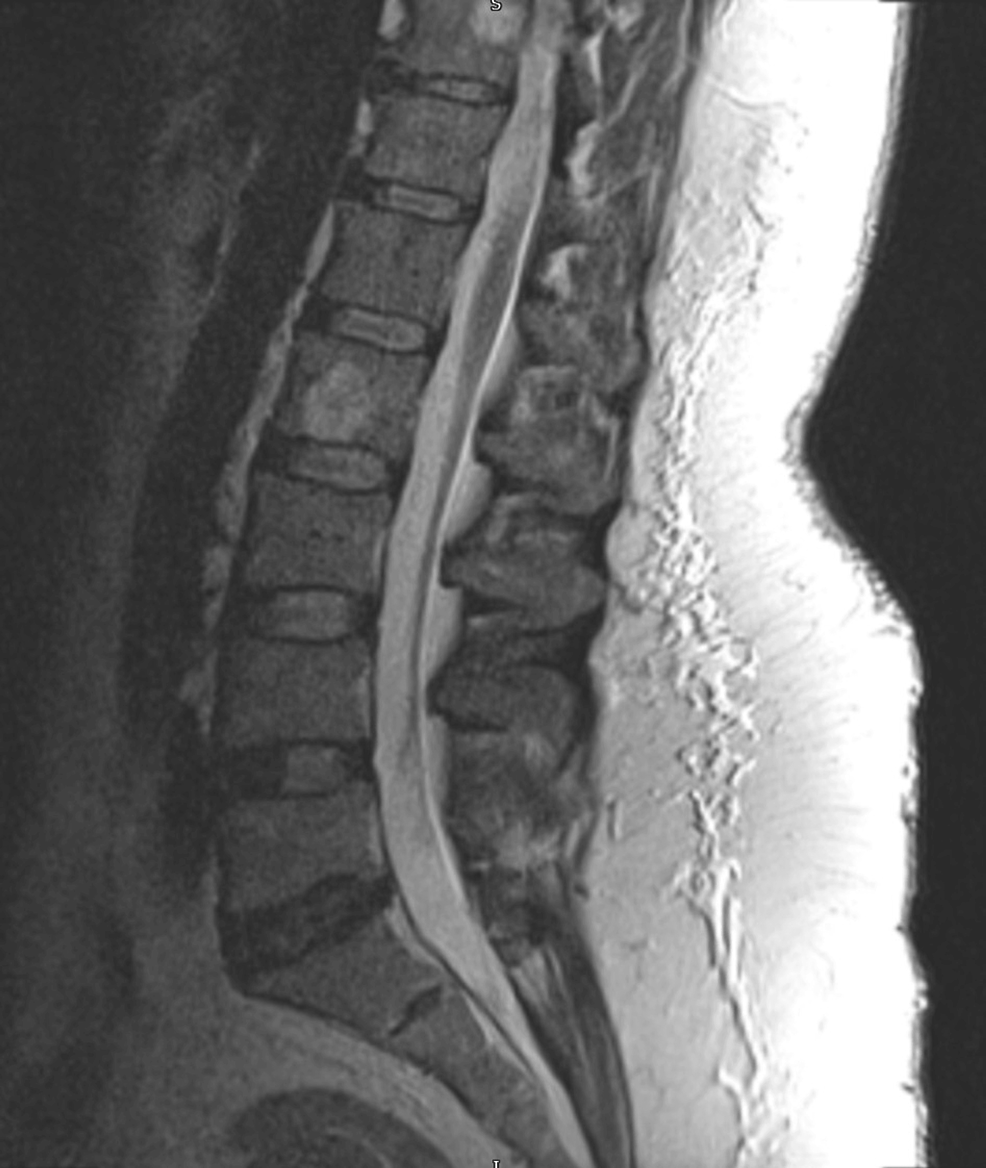

From www.cureus.com

Cureus Lumbar Facet Joint Fluid A Reliable Sign of Lumbar Instability Facet Joint Overgrowth Web facet joint disease is a condition in which the facet joints (also termed zygapophyseal joints) of the spine become a source of pain. Web facet hypertrophy is a degenerative disease that causes enlargement of the facet joints in the spine. This is a very common disease process (its prevalence increasing with age) and is a common source of disability. Facet Joint Overgrowth.